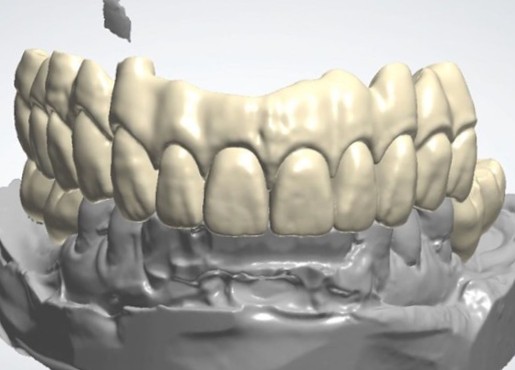

Digital & Aesthetics

Introducing a variety of smart technologies

and innovative production methods

to meet diverse customer needs.

This approach delivers beautiful results.

We ensure best-in-class technology,

integrating digital innovation with aesthetic excellence.